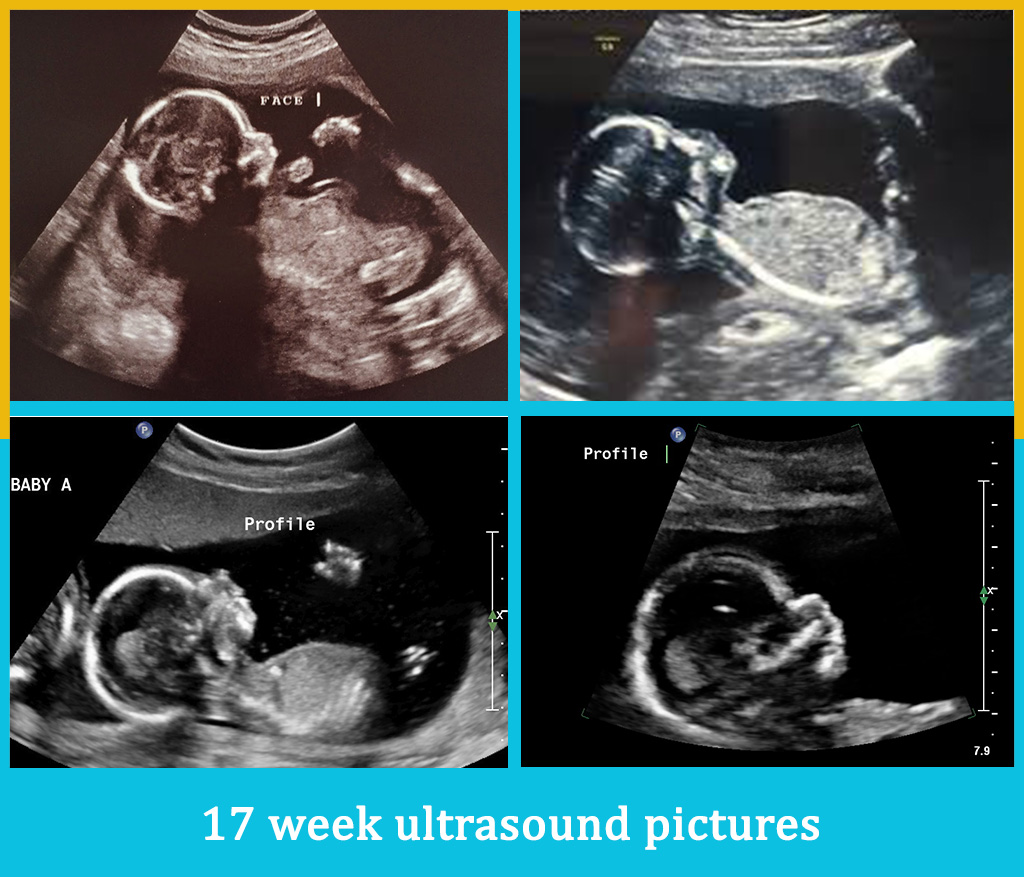

The 17th week of pregnancy | mother-top.com

The ultimate guide for your 19 week Fetal ultrasound …